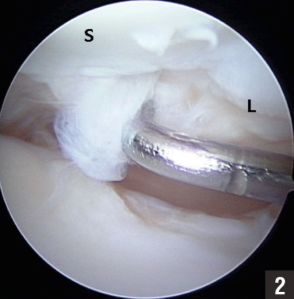

Voorbeeld van een kijkoperatie waarbij met camera en kleine instrumenten in de pols de operatie gedaan kan worden.

Operatiebeeld: het haakje dat u in beeld ziet is in het echt ongeveer 2 mm groot